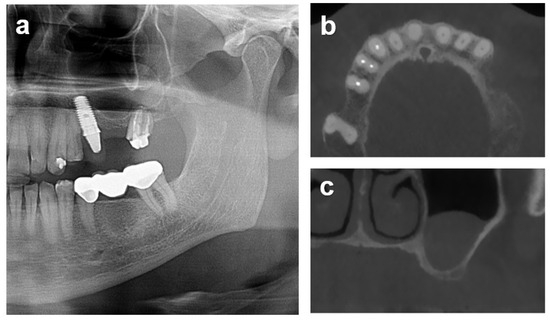

2.7.1. Case 1

2.7.2. Case 2

2.7.3. Case 3

3.2. Radiometric Assessment